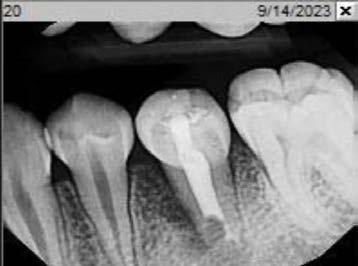

Cover: It’s a tricky situation. Patient with partial denture

Technique for extracting tooth or root tip from underneath fixed partial denture emphasizes use of magnification from dental loupes or dental surgical operating microscope for precision when performing technique-sensitive procedure. Case report.